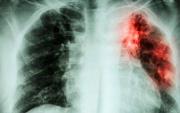

El brusco y preocupante aumento de casos de turberculosis en la Argentina, que se incrementó en un 38 por ciento respecto al promedio registrado en los diez años anteriores, en situaciones que las fuentes médicas relacionan a la caída en las tasas de vacunación y al... + más